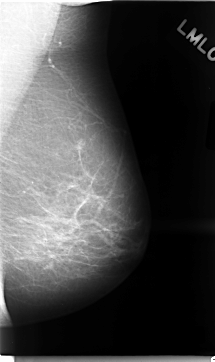

Digital Database for Screening Mammography

Volume: cancer_02 Case: C-0022-1

C_0022_1.LEFT_MLO

LEFT_MLO LINES 4696 PIXELS_PER_LINE 2792 BITS_PER_PIXEL 12 RESOLUTION 50 NON_OVERLAY

RIGHT_MLO LINES 4632 PIXELS_PER_LINE 2832 BITS_PER_PIXEL 12 RESOLUTION 50 OVERLAY

FILE: C_0022_1.RIGHT_MLO.OVERLAY

TOTAL_ABNORMALITIES 3

ABNORMALITY 1

LESION_TYPE MASS SHAPE IRREGULAR MARGINS MICROLOBULATED

ASSESSMENT 5

SUBTLETY 5

PATHOLOGY MALIGNANT

ABNORMALITY 2

ABNORMALITY 3

LESION_TYPE CALCIFICATION TYPE AMORPHOUS DISTRIBUTION CLUSTERED